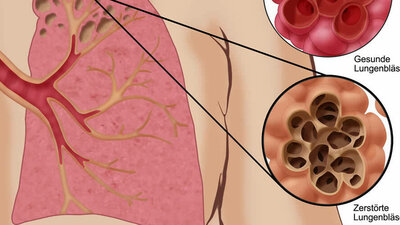

Bei einem Teil der Patienten dominiert diese Entzündung. Bei einem anderen greift die Krankheit zusätzlich die Lungenbläschen (siehe Grafik) an. Deren Aufgabe ist es, Sauerstoff aus der Atemluft ins Blut zu schleusen und das Stoffwechselprodukt Kohlendioxid in die Atemluft abzugeben. Bei einer COPD zerfallen die Wände der Lungenbläschen, sie platzen sozusagen. Die Fläche für den Gasaustausch verkleinert sich. Er funktioniert immer schlechter. Ein Sauerstoffmangel entsteht, obgleich die Lunge voller Luft ist. Der Fachbegriff lautet Lungenemphysem.

Eine COPD kann Bronchien und Lungenbläschen betreffen

© W&B/Dr. Ulrike Möhle